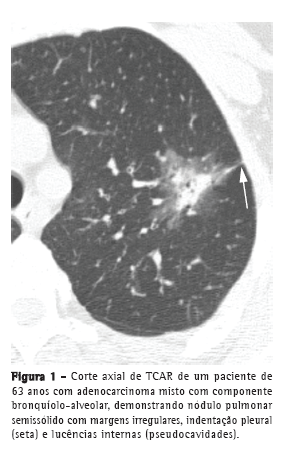

O nódulo pulmonar solitário, usualmente na periferia dos lobos superiores, é descrito como a manifestação tomográfica mais comum do CBA e AM-CBA.(12) A maioria desses nódulos são semissólidos, com componentes sólidos e em vidro fosco, exibindo margens irregulares e indentação pleural.(7) Embora a escavação seja rara na apresentação inicial, alguns nódulos podem ter lucências focais, conhecidas como pseudocavidades (Figura 1).(7,13) Pode haver escavação após o tratamento quimioterápico (Figura 2).